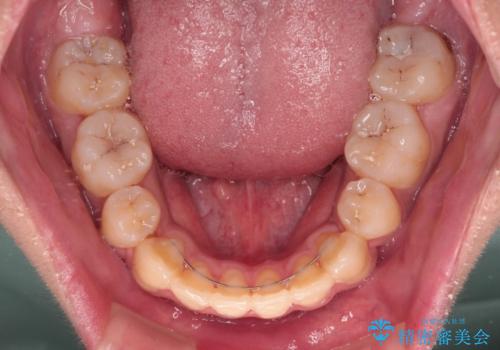

膨らんだ口元 ワイヤー装置での抜歯矯正

- 口元の突出感を気にして来院された患者様です。

上下前歯が著しく前突している状態であったので、上下左右の第1小臼歯4本を抜歯し、ワイヤー装置にて矯正治療を行うこととしました。

舌の突出癖により、前突になったと考えられたため、舌のトレーニングをしっかりと行うよう指導しました。

小学生の頃に上顎前歯をぶつけ、歯の一部が破損している状態であったので、歯根が歯槽骨と癒着して移動しない可能性がありましたが、無事に治療を終えることができました。

受験勉強と重なり、舌のトレーニングが十分に行えず、高校生としてはやや長期間の治療となりました。